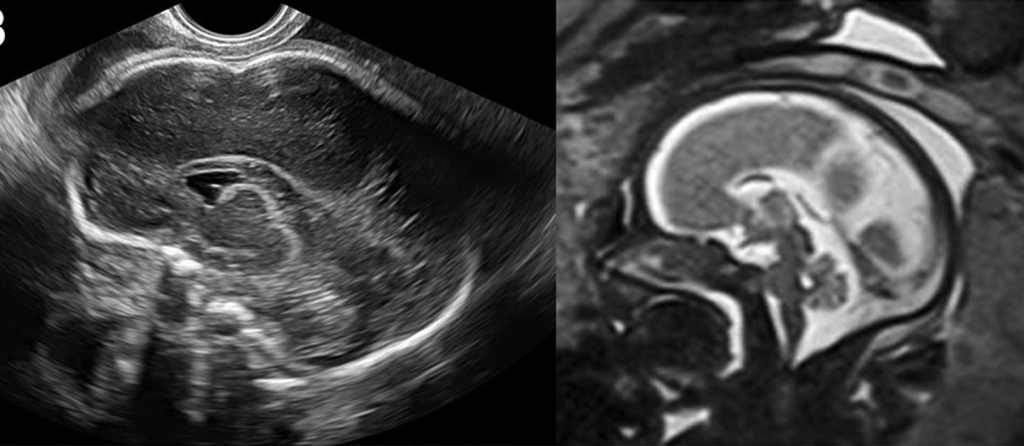

Bất sản thể chai bán phần trên siêu âm được chẩn đoán như thế nào?

Chẩn đoán dựa vào khảo sát mặt phẳng dọc giữa chuẩn. Bác sĩ đánh giá trực tiếp cấu trúc thể chai. Có thể thấy thể chai mỏng hoặc thiếu một đoạn.

MRI não thai có cần thiết không?

MRI não thai giúp đánh giá chi tiết hơn cấu trúc não. Đặc biệt là vỏ não và chất trắng.

MRI thường được thực hiện sau tuần 20. Giá trị cao hơn sau tuần 26 khi cấu trúc vỏ não phát triển rõ hơn.

Trong các bất thường thể chai, MRI có thể phát hiện thêm tổn thương phối hợp mà siêu âm chưa thấy rõ. Điều này ảnh hưởng trực tiếp đến tư vấn tiên lượng.

Giá trị của MRI phụ thuộc chất lượng siêu âm ban đầu.